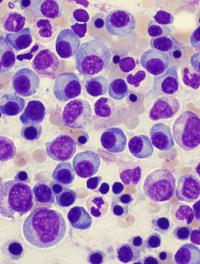

Les syndromes myélodysplasiques (SMD) constituent un groupe hétérogène d’hémopathies caractérisées par une dysplasie de la moelle osseuse [...]

Les syndromes myélodysplasiques (SMD) de faible risque correspondent aux catégories risque faible et risque intermédiaire 1 de l’IPSS [...]